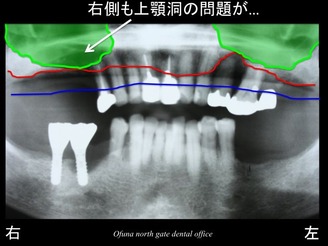

次に問題があったのが、上顎右側奥歯です。

この部分も骨吸収と上顎洞の問題がありました。

骨の高さがほとんとありませんでした。

実際に上顎洞を線で書いてみましょう!

先程解説しましたように この緑線の内側は骨ではありません。

ただの空洞です。

さらに見やすくするために 上顎洞を緑色で塗りつぶしてみましょう!

現状では 骨吸収と 上顎洞の存在のため、インプラントを埋め込むことはできません。

骨の高さがほとんどないのです。